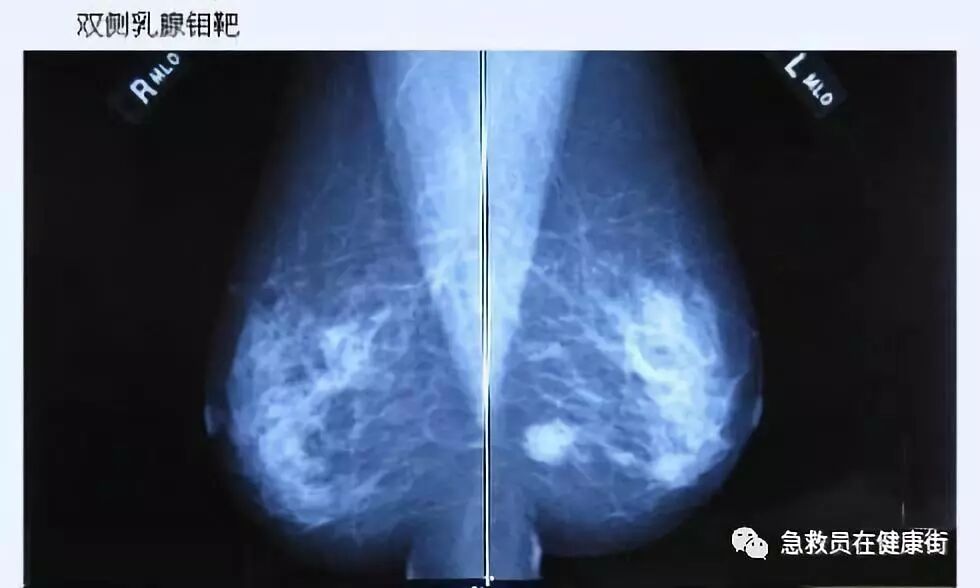

2. 钼靶片可见的局灶或可疑微小簇状钙化。

超声是乳腺检查的重要手段,有时可发现临床上无法触及且钼靶也未能显示的结节,即隐匿性乳腺结节。在这些乳腺结节中,有些结节虽然超声上存在可疑恶性征象,但穿刺病理结果却显示为良性。由于存在穿刺结果的假阴性可能,临床上对这类结节如何处置仍存在争议。来自韩国的 Moon 等人对这类隐匿性乳腺结节进行研究,其结果发表在 2016 年第 11 期的 J Ultrasound Med 杂志上。

作者回顾性分析了近 5 年间超声检查 BI-RADS 4 类以上、经穿刺病理证实为良性而临床上触摸不到以及钼靶检查阴性的 73 个病例共 78 个乳腺隐匿性结节。临床上触摸不到的结节定义为乳腺触诊在相应部位无明显的结节感或乳头无明显改变。钼靶检查阴性定义为从下诊断起 6 个月内钼靶检查未见异常。

78 个结节中,69 个经穿刺病理证实为乳腺良性乳头状瘤(平均大小 9 mm), 9 个为不典型乳头状瘤(平均大小 10 mm)。有 73 个结节的穿刺结果与 BI-RADS 分类一致,即分类为 4a 级而穿刺结果为良性,其余 5 个结节与 BI-RADS 分类不一致,即分类为 4a 级以上但穿刺结果为良性 。

在随后的临床治疗中,53 个结节行传统外科手术切除,12 个结节行真空辅助下旋转切除术,13 个结节行 2 年以上超声随访未发现异常变化,最终视为良性病变(图 1 和图 2)。

穿刺枪怎么升级乳腺穿刺术(三)_https://www.jmylbn.com_新闻资讯_第58张图 1 一 40 岁女性无症状性乳腺良性结节:超声检查示左乳结节大小 0.7 cm,边缘略成角,呈等回声(箭头);BI-RADS 分级为 4a 类,经穿刺病理证实为良性病变;钼靶检查提示为致密型乳腺,未见异常

穿刺枪怎么升级乳腺穿刺术(三)_https://www.jmylbn.com_新闻资讯_第59张图 2 一 45 岁女性因右乳疼痛就诊,超声发现左乳一 0.7 cm 结节,边界清晰,呈复杂囊性病灶,BI-RADS 分级为 4a 类;钼靶检查提示致密型乳腺;超声随访 27 个月后病灶增大至 1.3 cm(箭头所示),遂行外科手术切除,术后病理证实为不典型乳头状瘤